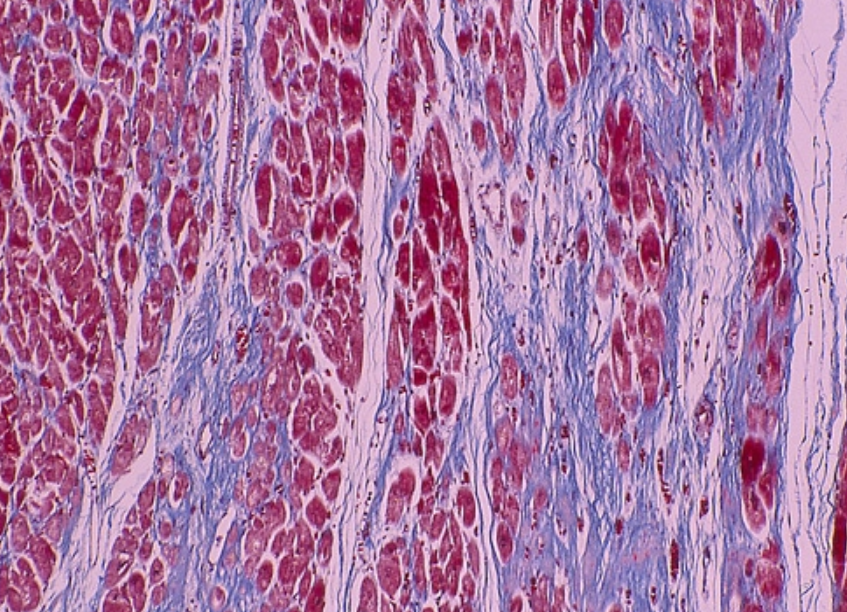

ÆÃȯÀ¿´¶Ú¾É¤ËÃÖ¤±¤ë¿´¶ÚÀ¸¸¡Ê¼Ë¡¤ÎÉÂÍý·×Âà³ØÅª¸¡Æ¤

³ÈÄ¥·¿¿´¶Ú¾É¤Î¿´ÅÅ¿Þ¤ÎÆÃħ¡§

¡¡³ÈÄ¥·¿¿´¶Ú¾É¤ËÆÃ°ÛŪ¤Ê¿´Åſ޽긫¤Ï¤Ê¤¤¡¥¤·¤«¤·¤Ê¤¬¤é¡¤¿´¶Ú¤ÎÀþ°Ý²½¡¤¿´Ë¼¿´¼¼¤Î³ÈÄ¥¡¤»É·ãÅÁƳ·Ï¤Î¾ã³²¡¤¿´ÉÔÁ´Åù¤ËͳÍ褹¤ëÇÈ·ÁÊѲ½¡¤ÉÔÀ°Ì®¤¬Ç§¤á¤é¤ì¤ë¡¥ÆÃ¤Ëº¸¼¼¤Î³ÈÄ¥¡¤Àþ°Ý²½¤¬¿Ê¹Ô¤¹¤ë¤È¡¤º¸¼¼¹âÅŰ̢·º¸¼¼ÈîÂç¡Ê³ÈÂç¡Ë¡¤r Çȸº¹â¡ÊÆÃ¤ËV1¤«¤éV3 ͶƳ¤Îpoor r progression¡Ë¡¤°Û¾ïQÇÈ¡¤QRSÉý±äĹ¡¤º¸Â¦¶»ÉôͶƳ¤Ë¤ª¤±¤ëVAT±äĹ¡¤ µÓ»Þ¥Ö¥í¥Ã¥¯¡¤ ¿´¼¼Æâ¥Ö¥í¥Ã¥¯¡¤ ST-TÊѲ½¤Ê¤É¤¬½Ð¸½¤¹¤ë¡¥º¸¼¼¤Î³ÈÄ¥¤¬¤µ¤é¤Ë¿Ê¹Ô¤¹¤ë¤È¡¤QRSÉý¤¬0.12Éäòͤ¨¡¤º¸µÓ¥Ö¥í¥Ã¥¯½ê¸«¤òÄ褹¤ë¤¬¡¤¤½¤ÎÇÈ·Á¤Ïº¸¼¼³ÈÂç¤òȼ¤ï¤Ê¤¤Ãæ¿õÀ¤Îº¸µÓ¥Ö¥í¥Ã¥¯¤È¤Ï°Û¤Ê¤ê¡¤QRSÇȤËÊ£¿ô¤Înotch¤ò´Þ¤à¤è¤¦¤Ê°Û¾ï¤ÊÇÈ·Á¡ÊËö¾¿À¤Îº¸µÓ¥Ö¥í¥Ã¥¯¡Ë¤È¤Ê¤ë¡¥¤Þ¤¿¡¤º¸¼¼¤ÎÀþ°Ý²½¤¬¶ËÅ٤˿ʹԤ¹¤ë¤È¡¤º¸¼¼¤Îµ¯ÅÅÎϤ¬Äã²¼¾Ã¼º¤·¤Æ¡¤º¸Â¦¶»ÉôͶƳ¤ÎRÇȤ¬ÃøÌÀ¤Ë¸º¹â¤·¡¤SÇȤ¬¼çÂΤζ»ÉôͶƳÇÈ·Á¤ò¼¨¤¹¡Ê±¦µÓ¥Ö¥í¥Ã¥¯Îã¤ò½ü¤¯¡Ë¤È¤È¤â¤Ë¡¤»Í»èͶƳ¤ÏÄãÅŰ̲½¤¹¤ë¤è¤¦¤Ë¤Ê¤ë¡¥°ìÊý¡¤±¦¼¼¤Î³ÈÂ硤°µÉé²Ù¤¬À¸¤¸¤ë¤È±¦Â¦¶»ÉôͶƳ¤ÇTÇȤ¬±¢Å¾²½¤·¡¤¤½¤ì¤¬¤è¤êÃøÌÀ¤Ë¤Ê¤ë¤ÈV4¡¤V5ͶƳ¤Þ¤ÇT±¢Å¾¤¬Çȵڤ¹¤ë¤¬¡¤Æ±»þ¤Ëº¸¼¼³ÈÂ礬¸ºß¤¹¤ë¤È¡¤¤½¤ÎÊѲ½¤ÏÌÜΩ¤¿¤Ê¤¯¤Ê¤ë¡¥

ÈîÂç·¿¿´¶Ú¾É1 Dagger-like Q Waves